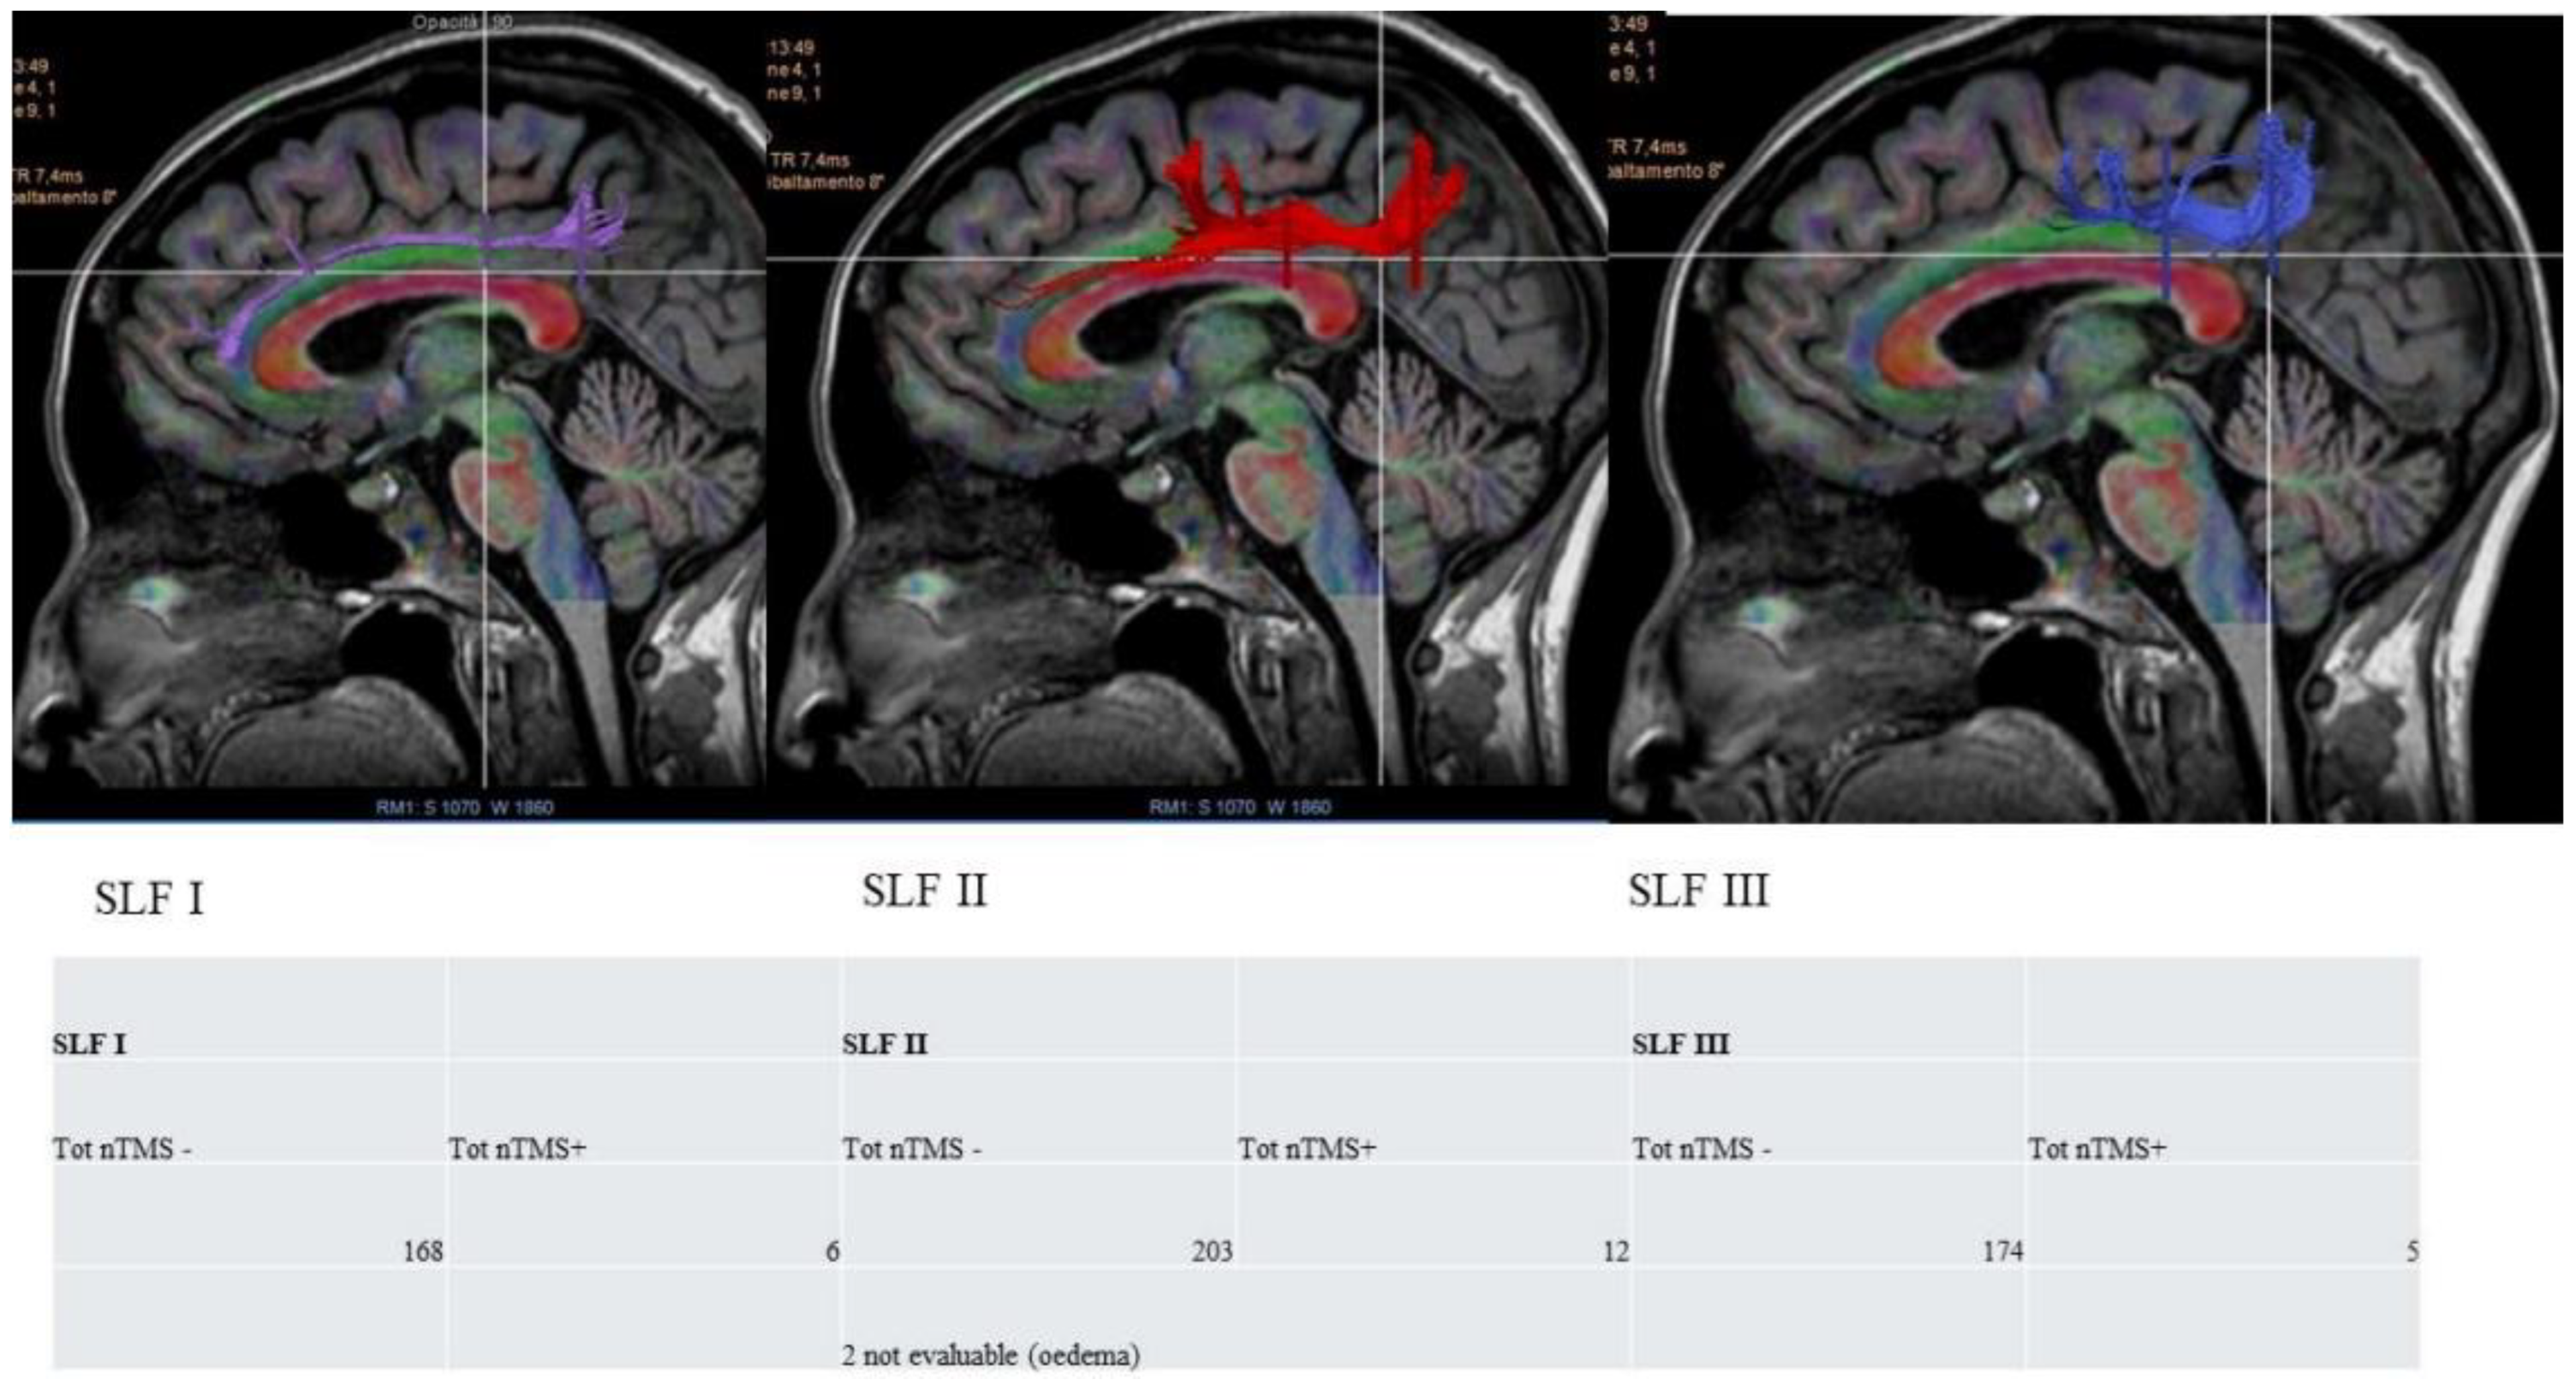

3.2. VS Network: nTMS-Based Tractography and nTMS Mapping

- the white matter fibre tracks underneath the VS network, analysing the predominant role of the three branches of the SLF;

4.4. nrTMS Mapping and DTI Tractography